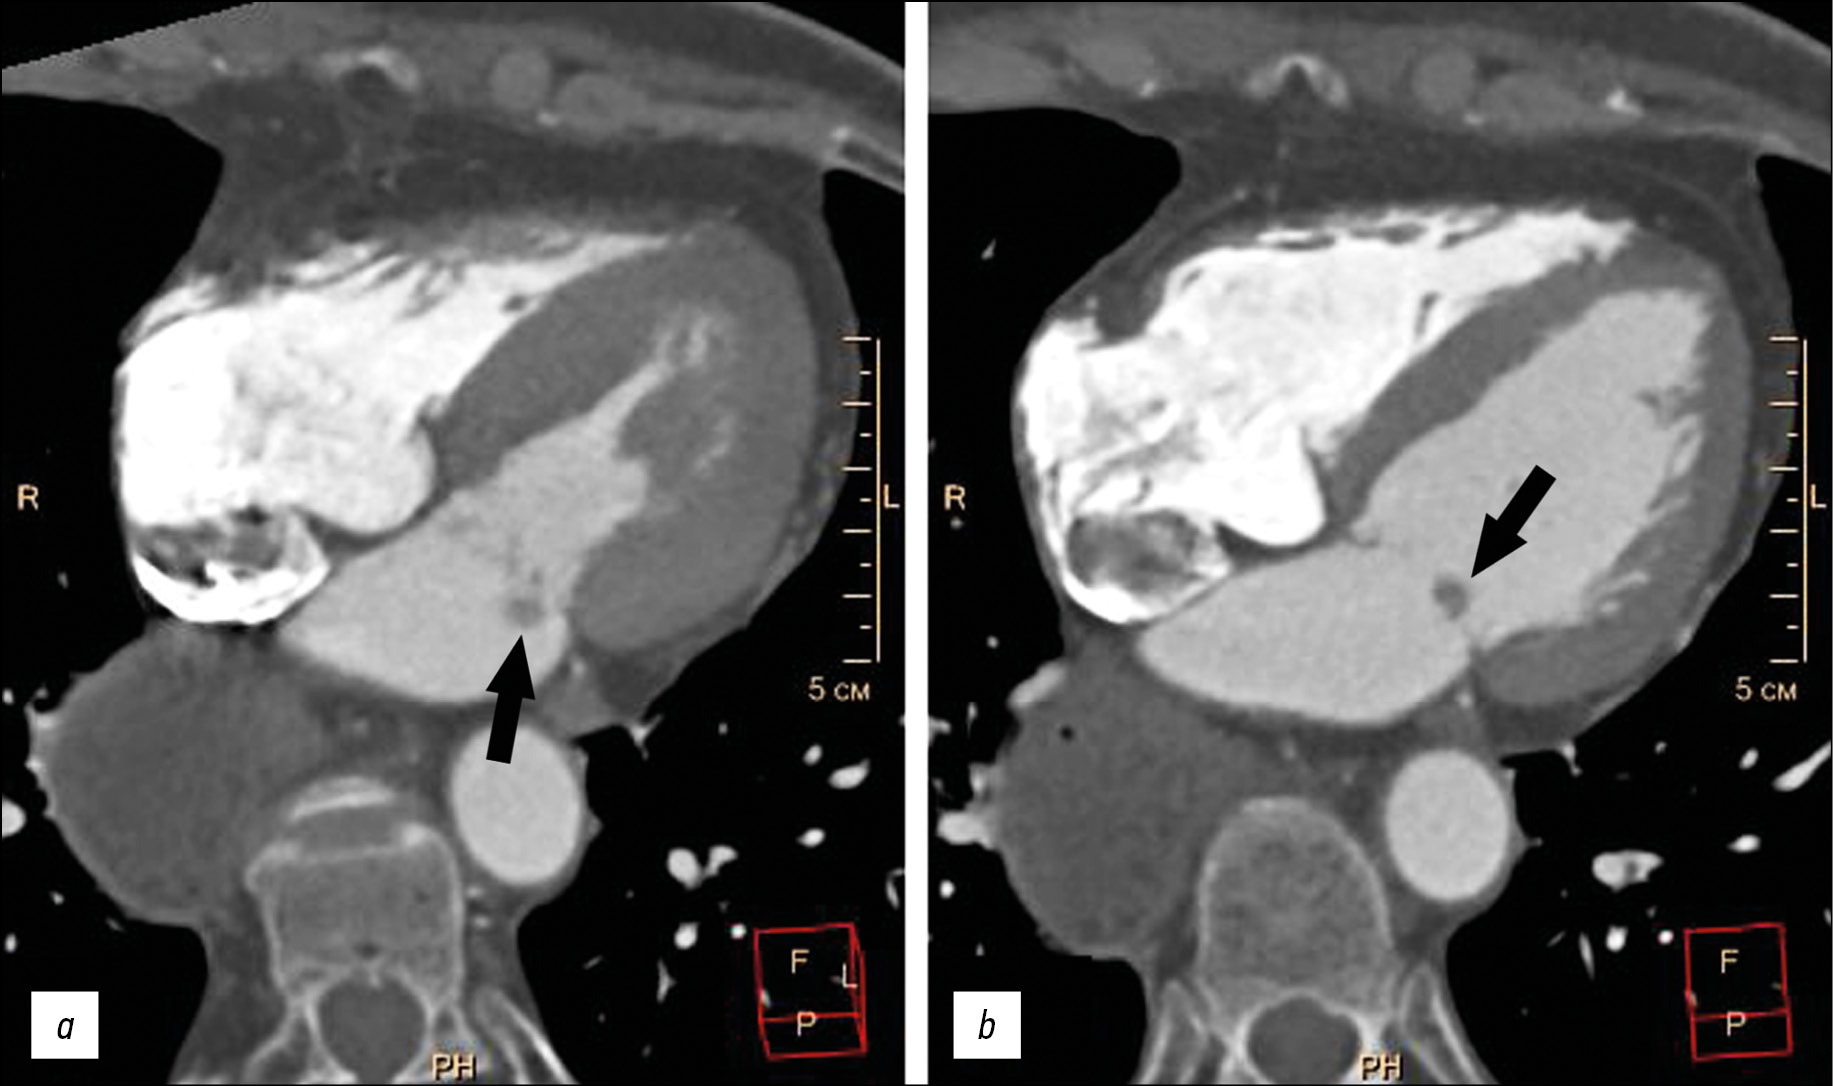

Computed tomography revealed no additional volumetric masses or areas of inflammatory infiltration in the pulmonary tissue. The stomach was visualized in the bed of the removed esophagus without pathological volumetric masses at this level. The examination revealed no pronounced coronary artery narrowings. An additional volumetric mass measuring 5–9 mm, round in shape, with clear irregular contours, and displaced together with the valve leaflet into the left ventricular cavity during atrial systole was visualized on the atrial surface of the posterior mitral valve leaflet (Fig. 1).

Fig. 1. Multispiral computed tomography of thoracic organs, four-chamber planar heart reconstruction, arterial contrast phase: а, left ventricular systolic phase; b, left ventricular diastolic phase. Additional rounded structure on the posterior mitral valve leaflet (black arrows).